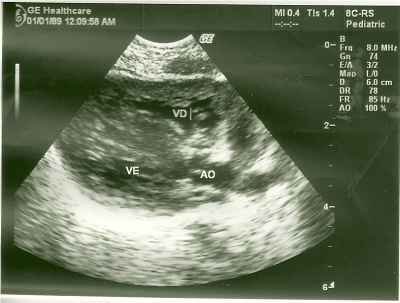

At the echocardiographic examination, an important septal hypertrophy was observed obstructing the left ventricular outflow tract (Figures 1, 2).

Figure 1. Long parasternal cut showing important septal hypertrophy.

Figure 2. Long parasternal cut with the heart in systole demonstrating obstruction of the left ventricular outflow tract by hypertrophy.